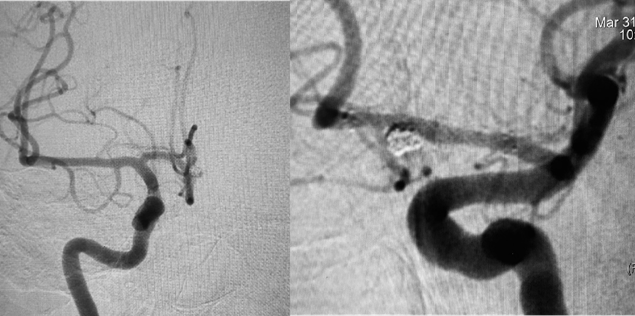

A 35-year-old previously healthy woman presented in emergency department complaining of severe headache, with a Grade 2 Hunt and Hess score. Neurological status was unremarkable. A computed tomography (CT) scan showed SAH (Modified Fisher Scale grade I) and the cerebrospinal fluid (CSF) sample showed 12.000 RBC/CC. Nevertheless, CT angiography did not depict any saccular aneurysm. Due to high suspicion, a three-dimensional rotational angiography was performed on day two, but showed only some minor AComA wall irregularities close to the left A1/A2 junction (Figure 1A). A second angiogram was performed 6 days later in order to elucidate the cause of the SAH and revealed a small pseudoaneurysm at this site (Figure 1B). Considering the acute morphological changes and the previous blending, we indicated urgent treatment. Microsurgical clipping occlusion of the AComA was discarded as an option since the lesion stretched out to the left A1/A2 segment. Since right A2 segment was supplied by right A1 segment, we decided to occlude AComA and the pseudoaneurysm with coiling and perform endovascular reconstruction of the left A1/A2 segments with a Flow Diverter Stent (FDS). The procedure was performed under general anesthesia and systemic heparinization (8000 IU during the procedure). The AComA occlusion was achieved with remodeling technique. A Scepter XC balloon 4 x 11m (Microvention Endovascular Inc., CA, USA) protected the left A1/A2 junction and three Microplex coils (Microvention Endovascular Inc., CA, USA) were detached through a Headway 17 microcatheter (Microvention Endovascular Inc., CA, USA). Finally, 2,5 x 14 x 20 mm Fred Jr Embolization Device (Microvention Endovascular Inc., CA, USA) (Figure 2) was placed through a Headway 21 microcatheter (Microvention Endovascular Inc., CA, USA), covering all the A1/A2 junction. Immediately after its placement, we administered intravenous abciximab 0.25 mg/kg bolus and maintenance dose for 12 hours. Dual antiplatelet therapy was initiated in the following day with clopidogrel 75 mg and aspirin 100 mg and kept for three months while aspirin was sustained for one year. External ventricular derivation was not required since there was no ventriculomegaly. Patient presented no evidence of new neurological deficits or complications such as rebleeding, regrowth, vasospasm, stent occlusion/stenosis or stroke. Control angiogram performed three months later confirmed exclusion of both pseudoaneurysm and the AComA (Figures 3) without any persistent arterial wall irregularity. Patient remained clinically stable with mRs 0.

Figure 2 Treatment images showing the initial aspect on work projection (E), the pseudo aneurysm coiling by remodeling technique (F), the FDS placement (G and H) and the final aspect in non subtracted (I) and subtracted (J) images.

Figure 3 Frontal right ICA angiogram (L) and Oblique left ICA angiogram (M), at 6 months follow-up, showing stable pseudoaneurysm occlusion and a normal aspect of the left A1/A2 junction.